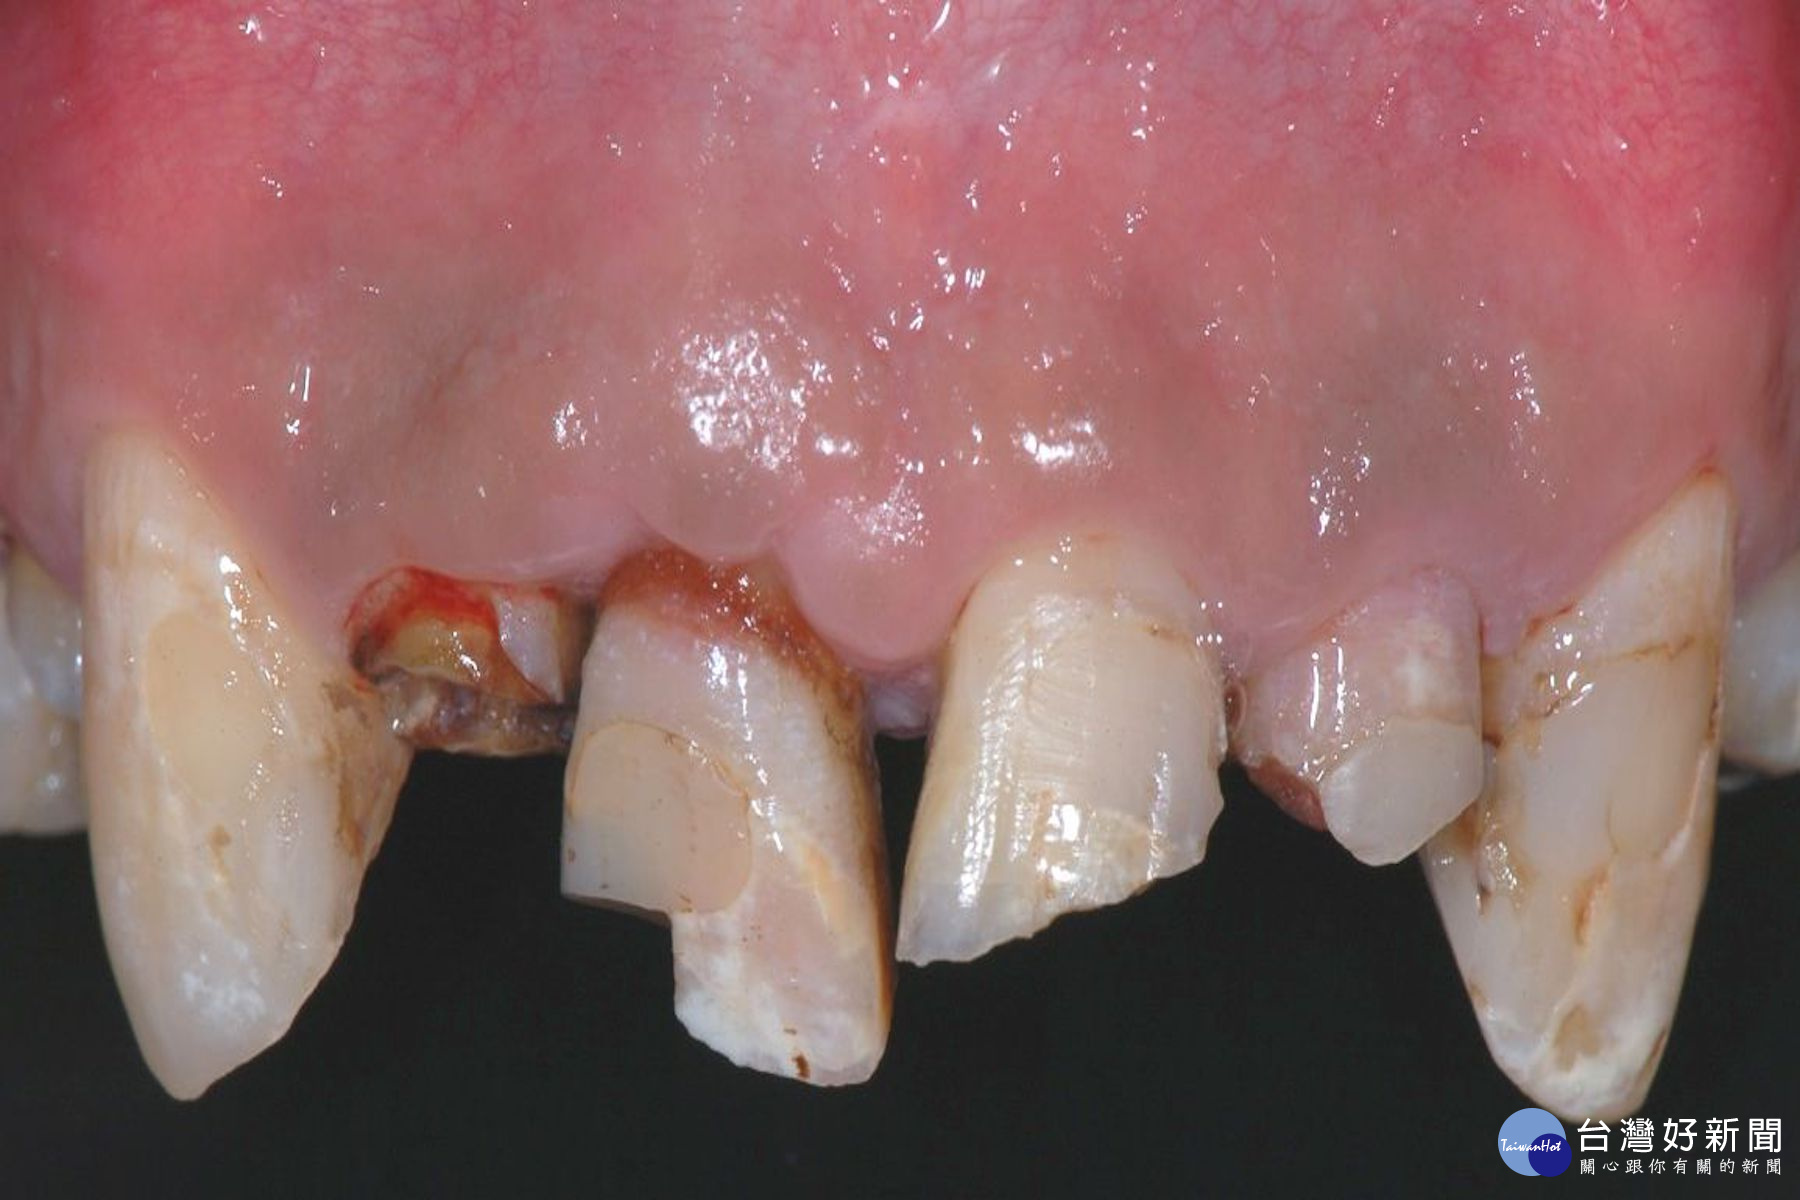

牙齒撞傷分成兩種,一種是整顆牙齒完整脫落,掉出齒槽骨;另一種是牙齒斷掉一部分,一部分還在口內。牙髓病科主治醫師賴曉錞說,整顆牙齒脫落,會因爲掉落口腔外的時間長短,及脫落牙齒的保存方式,讓治療方式和結果不同;牙齒斷裂,則視斷裂的情況和牙周韌帶是否受傷,來決定治療方式和預後。

若脫落的牙齒保存在適當的溶液中,並能在一小時內放回口內原位,牙齒有比較高的機率能保留下來,但後續需要定時且長期的追蹤。牙髓病科主治醫師賴曉錞認為,若牙齒脫落後保存不當、牙齒脫落時間過長、牙齒表面受損嚴重等,可能在追蹤的過程中需要做根管治療,甚至因為後續牙根發炎嚴重導致牙根吸收而需拔除。